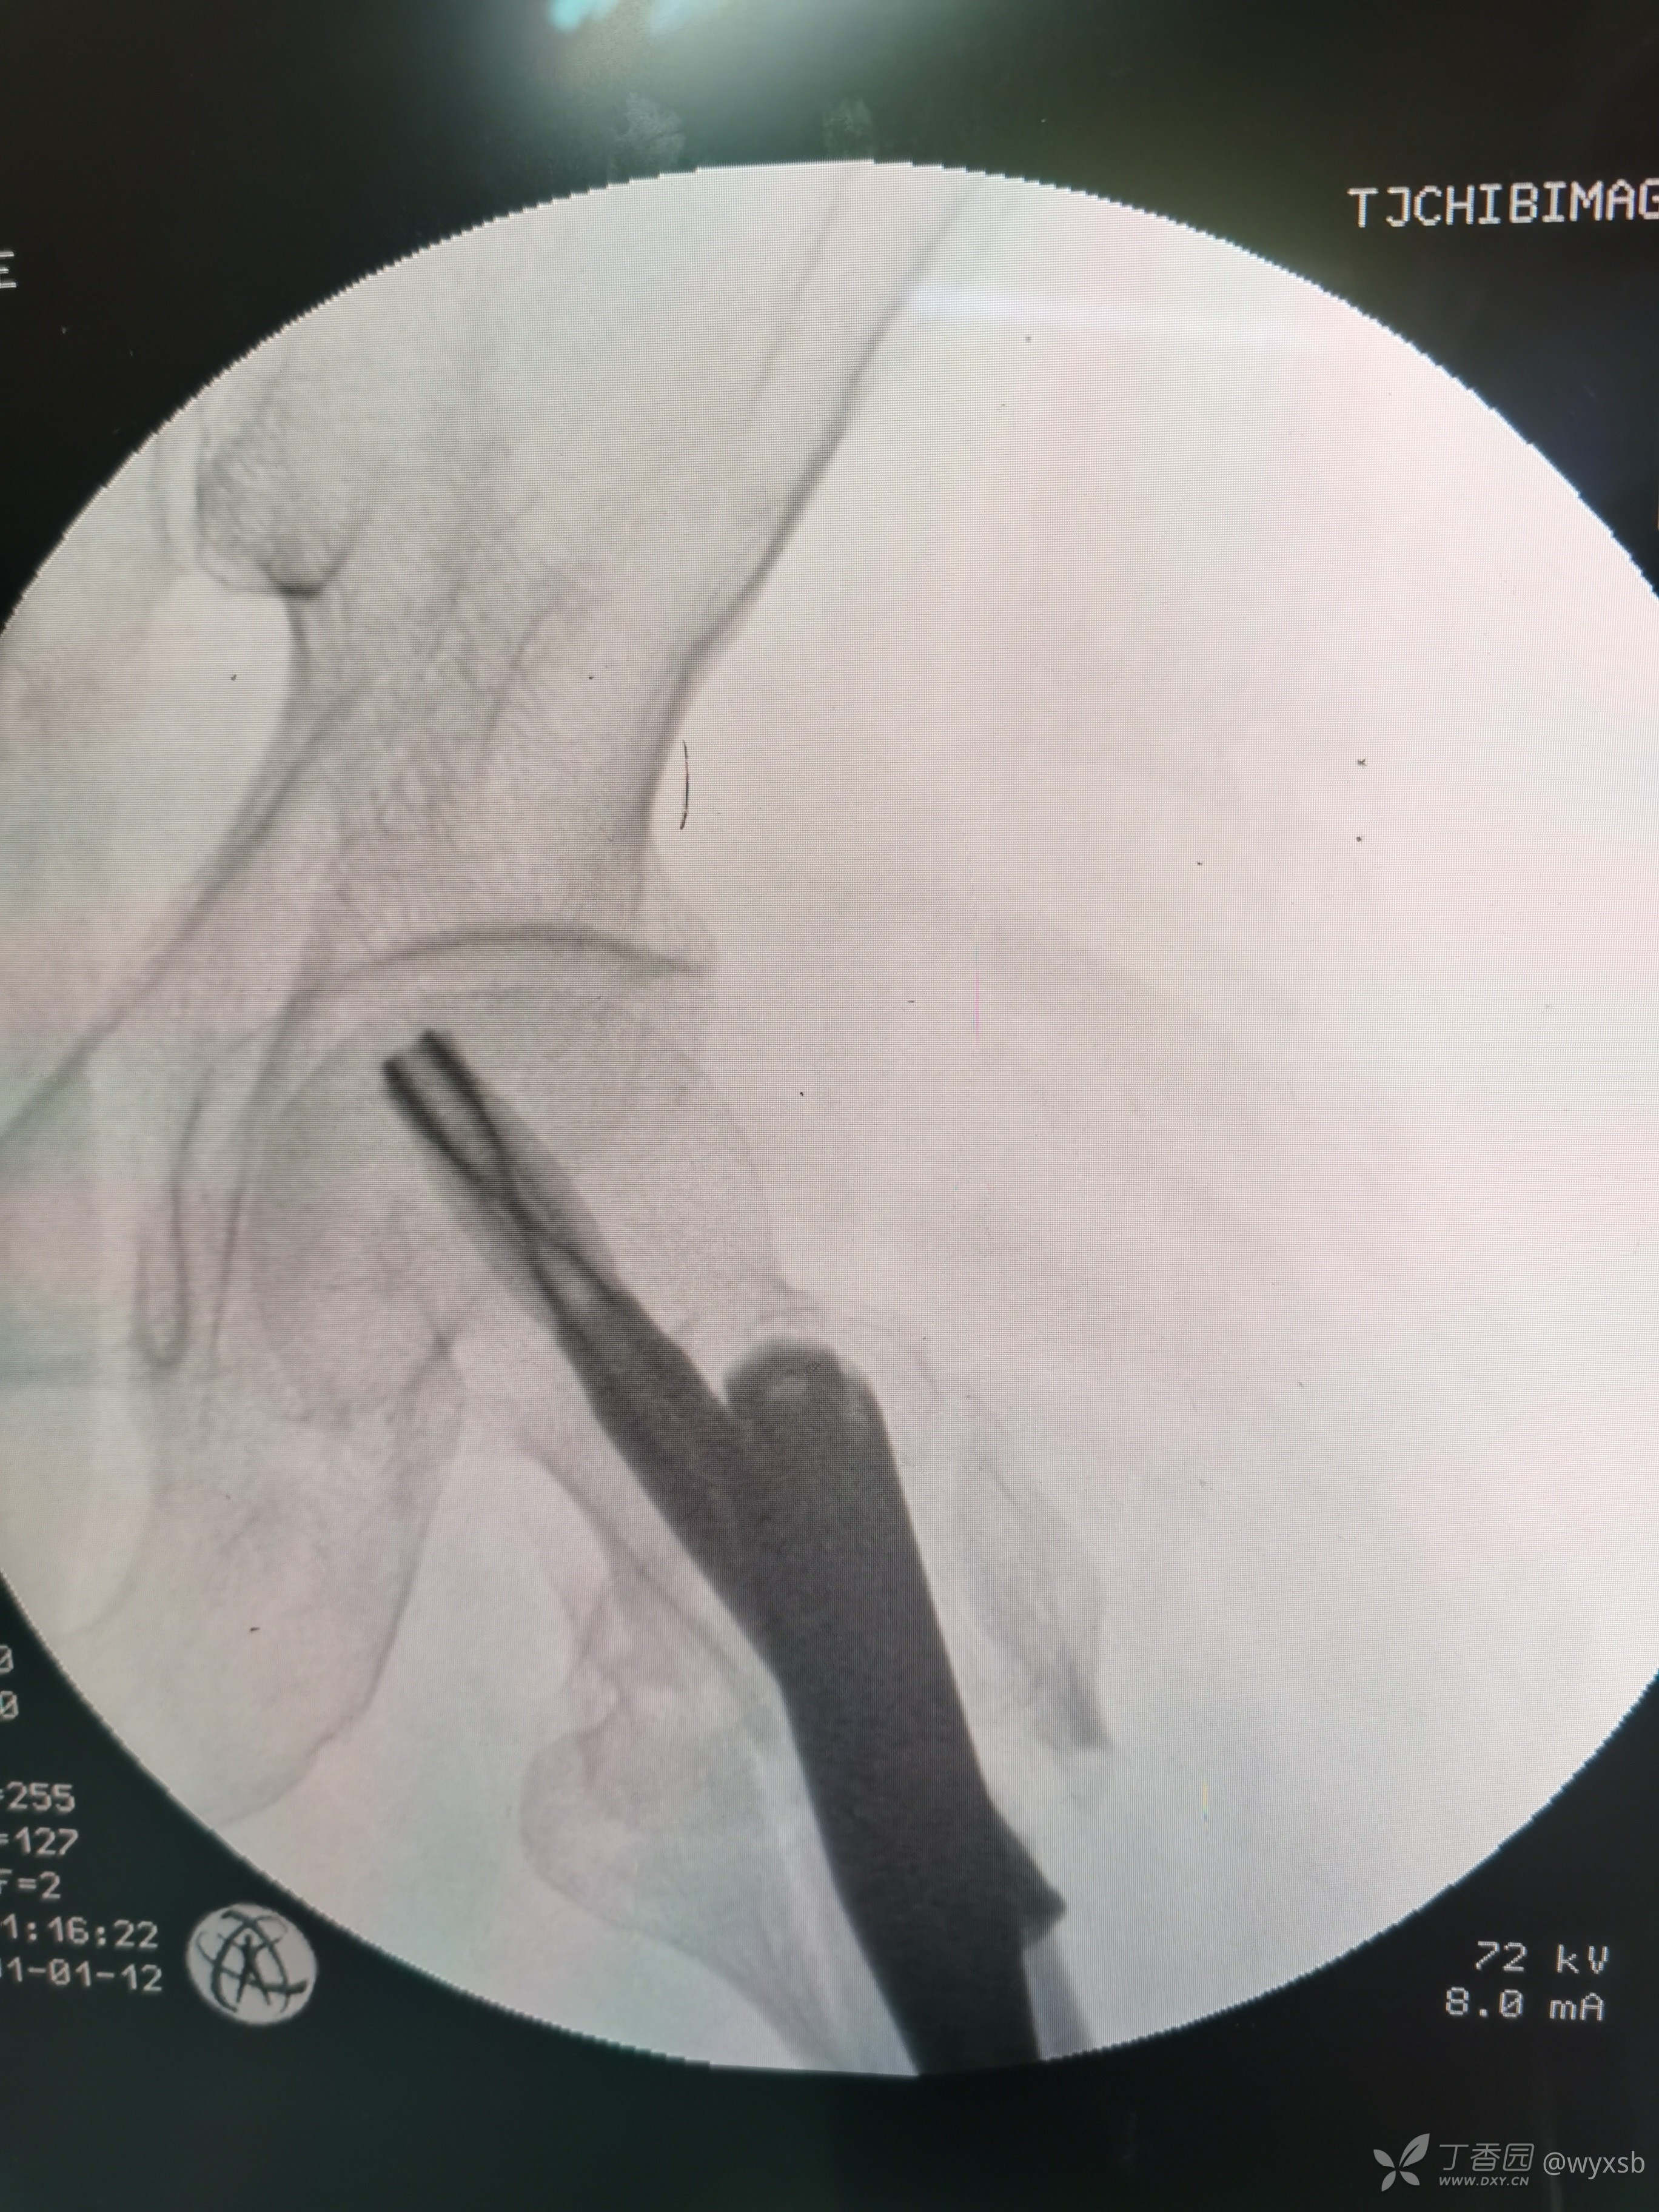

术中植钉情况

术中透视